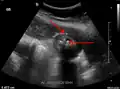

Right upper quadrant abdominal ultrasound is most commonly used to diagnose cholecystitis.[1][26][27] Ultrasound findings suggestive of acute cholecystitis include gallstones, pericholecystic fluid (fluid surrounding the gallbladder), gallbladder wall thickening (wall thickness over 3 mm),[28] dilation of the bile duct, and sonographic Murphy's sign.[13] Given its higher sensitivity, hepatic iminodiacetic acid (HIDA) scan can be used if ultrasound is not diagnostic.[13][14] CT scan may also be used if complications such as perforation or gangrene are suspected.[14]

Acute cholecystitis as seen on ultrasound. The closed arrow points to gallbladder wall thickening. Open arrow points to stones in the GB -